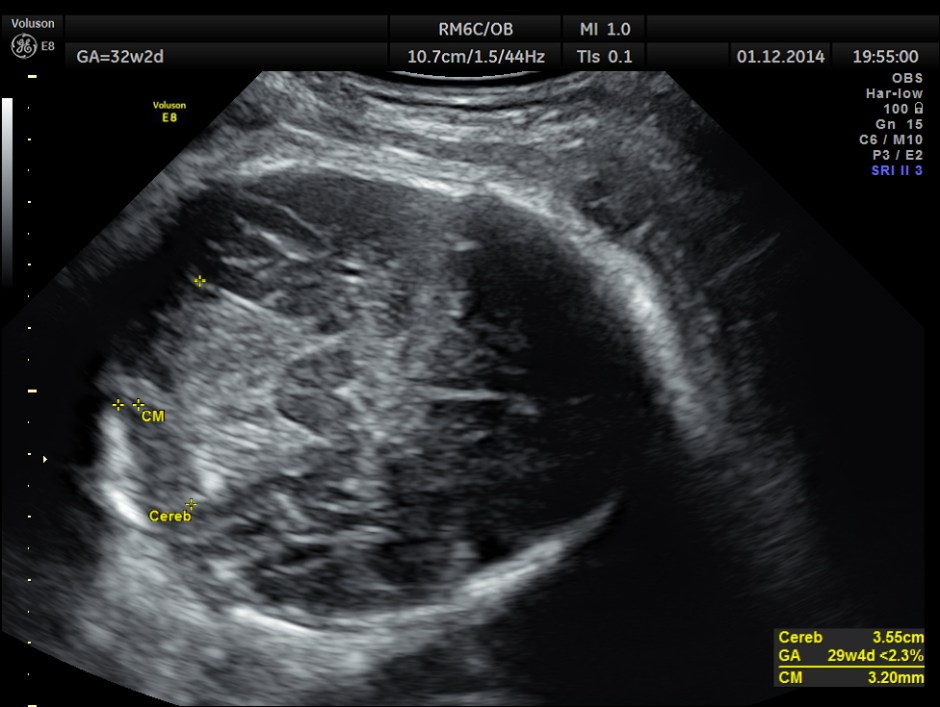

Hydrocephalus is seen ; Cisterna magna appeared somewhat compressed.

Careful examination revealed a neural tube defect with meningo myelocele at the lumbo sacral level.

Spinal deformity was also noted.

From the ultrasound point of view , we should always look carefully at the spine , in all the cases of hydrocephalus.